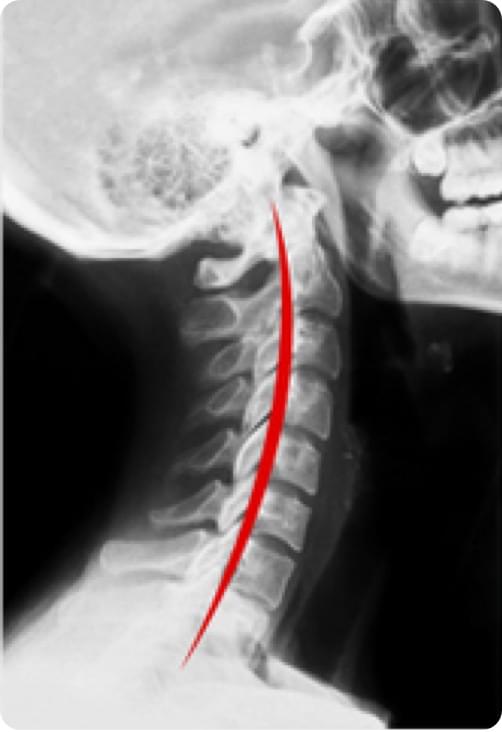

曲度初步改善